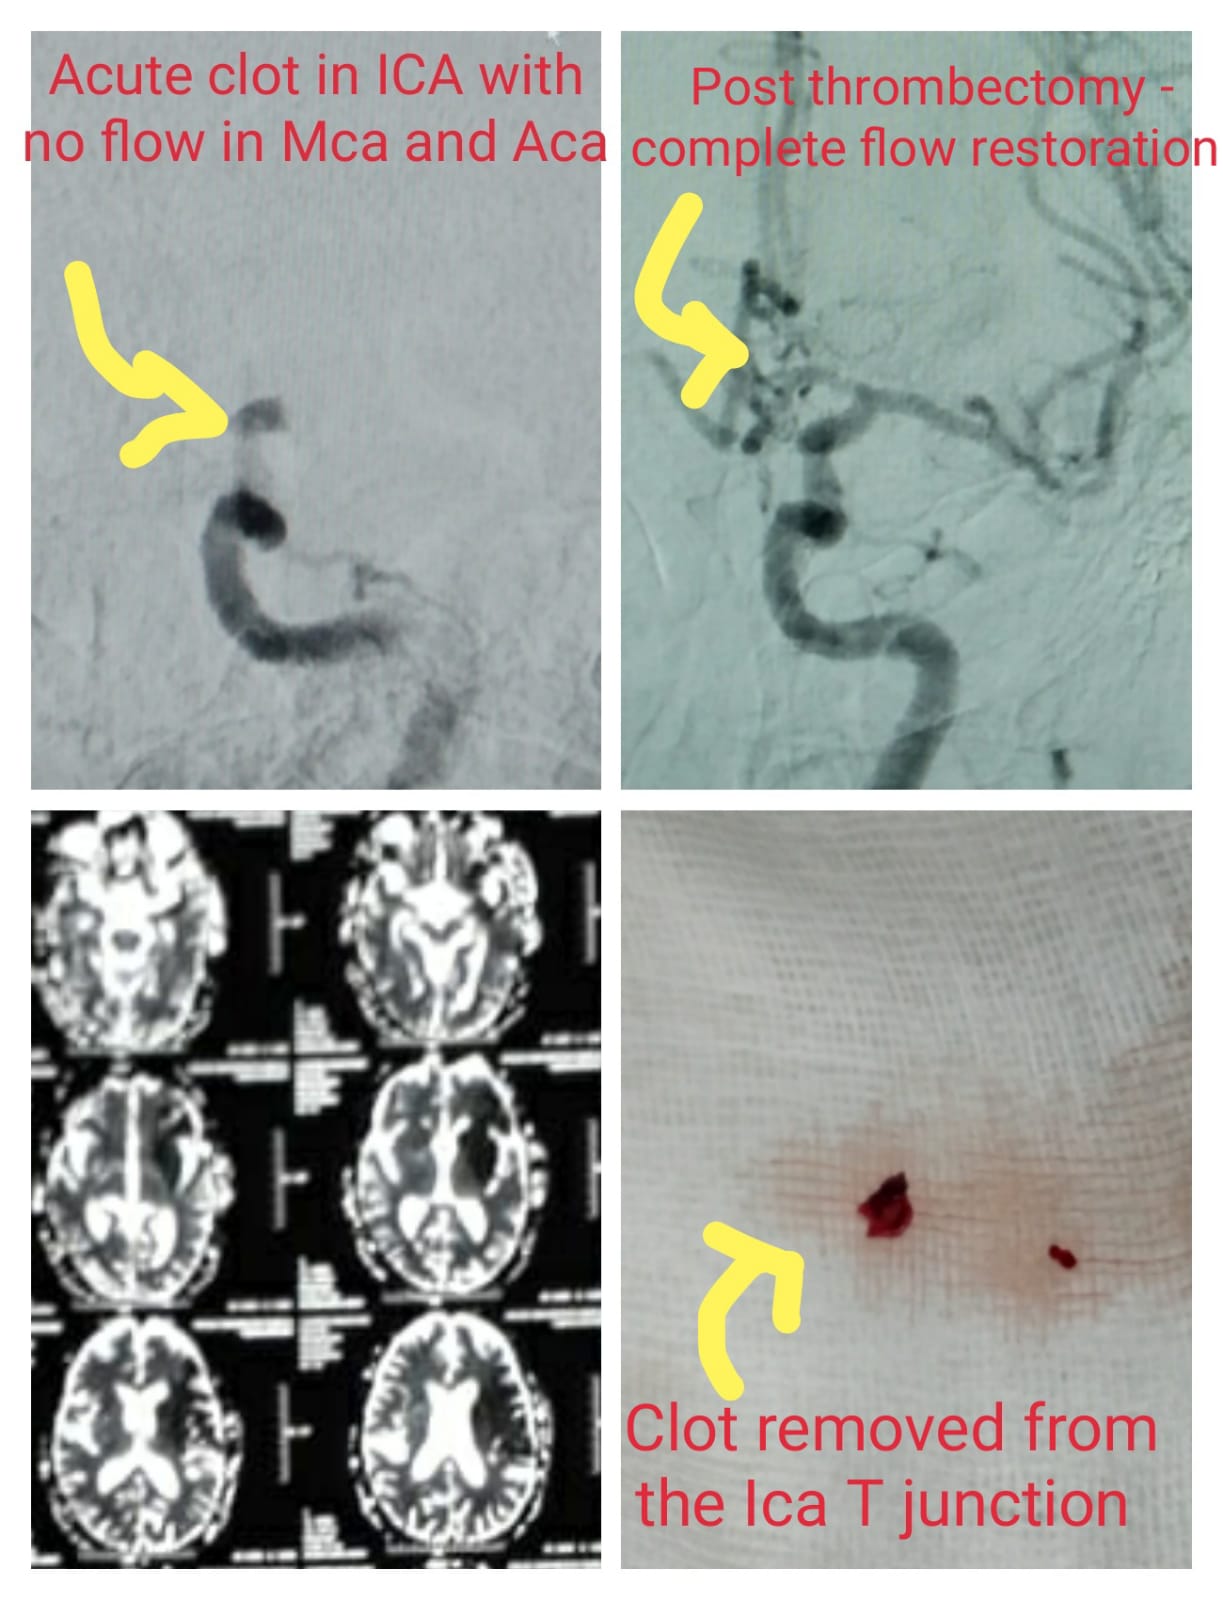

Thrombectomy Performed in Internal Carotid Artery. Pre-procedure- Acute clot in ICA with No flow IN MCA & ACA, Post Procedure- Complete blood flow restoration post Thrombectomy & Clot removed from the ICA T JUNCTION